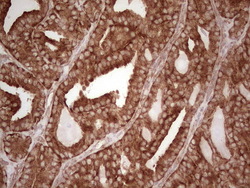

- Main image

- Experimental details

- Immunohistochemical staining of paraffin-embedded Adenocarcinoma of Human endometrium tissue using anti-WIBG mouse monoclonal antibody. (Heat-induced epitope retrieval by 1 mM EDTA in 10mM Tris, pH8.5, 120C for 3min, TA806496)

- Validation comment